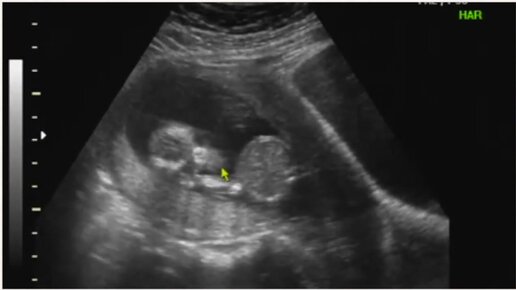

УЗИ на 15 неделе беременности

Медицинский женский центр